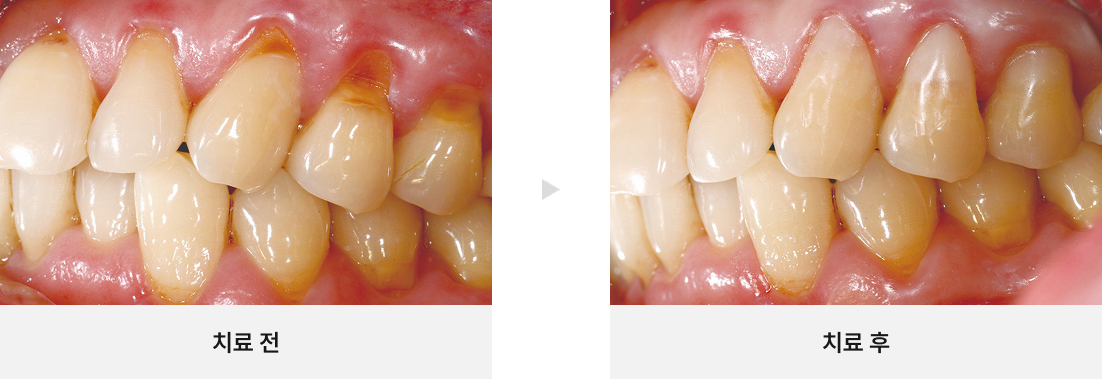

CASE.03

뿌리 끝에 염증이 있는 치아 살리기